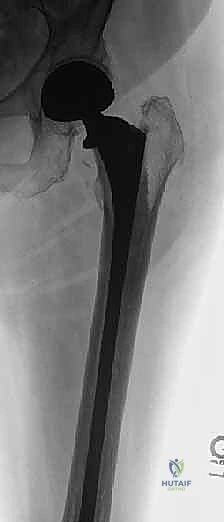

- اختيار نوع المفصل الاصطناعي: بناءً على صور الأشعة المقطعية، يحدد الجراح نوع المفصل. في حالات الأورام، غالباً ما تُستخدم مفاصل ذات جذوع طويلة (Long-stem prostheses) لتجاوز منطقة الورم وتثبيت المفصل في العظم السليم أسفل الآفة. كما تُستخدم تقنية الأسمنت العظمي (Bone Cement - PMMA) بكثافة لتوفير استقرار فوري للمفصل والسماح للمريض بالمشي في اليوم التالي.

الخطوة 4: تحضير عظم الفخذ وتثبيت الجذع (Femoral Stem Insertion)

- يتم تجويف القناة النخاعية داخل عظم الفخذ لتتناسب مع حجم الجذع المعدني (Stem).

- في مرضى السرطان النقيلي، يُفضل استخدام الأسمنت العظمي لتثبيت الجذع. الأسمنت العظمي لا يعمل كصمغ فقط، بل كحشوة تملأ الفراغات التي تركها الورم وتوفر دعماً ميكانيكياً فورياً.

- يتم وضع رأس معدني أو خزفي (Ceramic Head) على قمة الجذع.